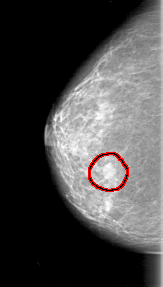

D_4001_1.RIGHT_CC

RIGHT_CC LINES 4291 PIXELS_PER_LINE 2431 BITS_PER_PIXEL 12 RESOLUTION 43.5 OVERLAY

FILE: D_4001_1.RIGHT_CC.OVERLAY

TOTAL_ABNORMALITIES 1

ABNORMALITY 1

LESION_TYPE MASS SHAPE OVAL MARGINS OBSCURED

ASSESSMENT 0

SUBTLETY 5

PATHOLOGY BENIGN

TOTAL_OUTLINES 1

BOUNDARY